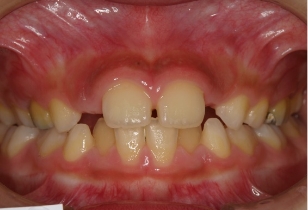

2025年夏、伊藤矯正歯科医院は抜歯を伴う矯正治療を行った症例の術後の安定度について統計的調査を行いました。その結果この症例のように、後戻りが最も現れやすいと言われる下の歯並びの前歯の部分で、他の矯正法に比べて大変に安定しているという結果が出ました。

安定調査症例2